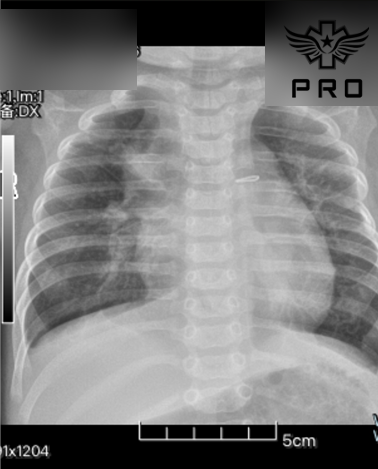

청생증과 심한 호흡곤란으로

초음파 검사에서 난원공단락, 삼천판역류, 우심실 우심방 확장 소견이 있었습니다.

이로인해 우심실기능이상이나 삼천판역류로 인하여 우심방 압력이 높아지며

입원 당시 고유량 산소가 필요하였으며

약물 증량후 상태도 점점 안정되어 청색증이 없어졌고

저유량 산소로 포화도도 잘 측정되었어요